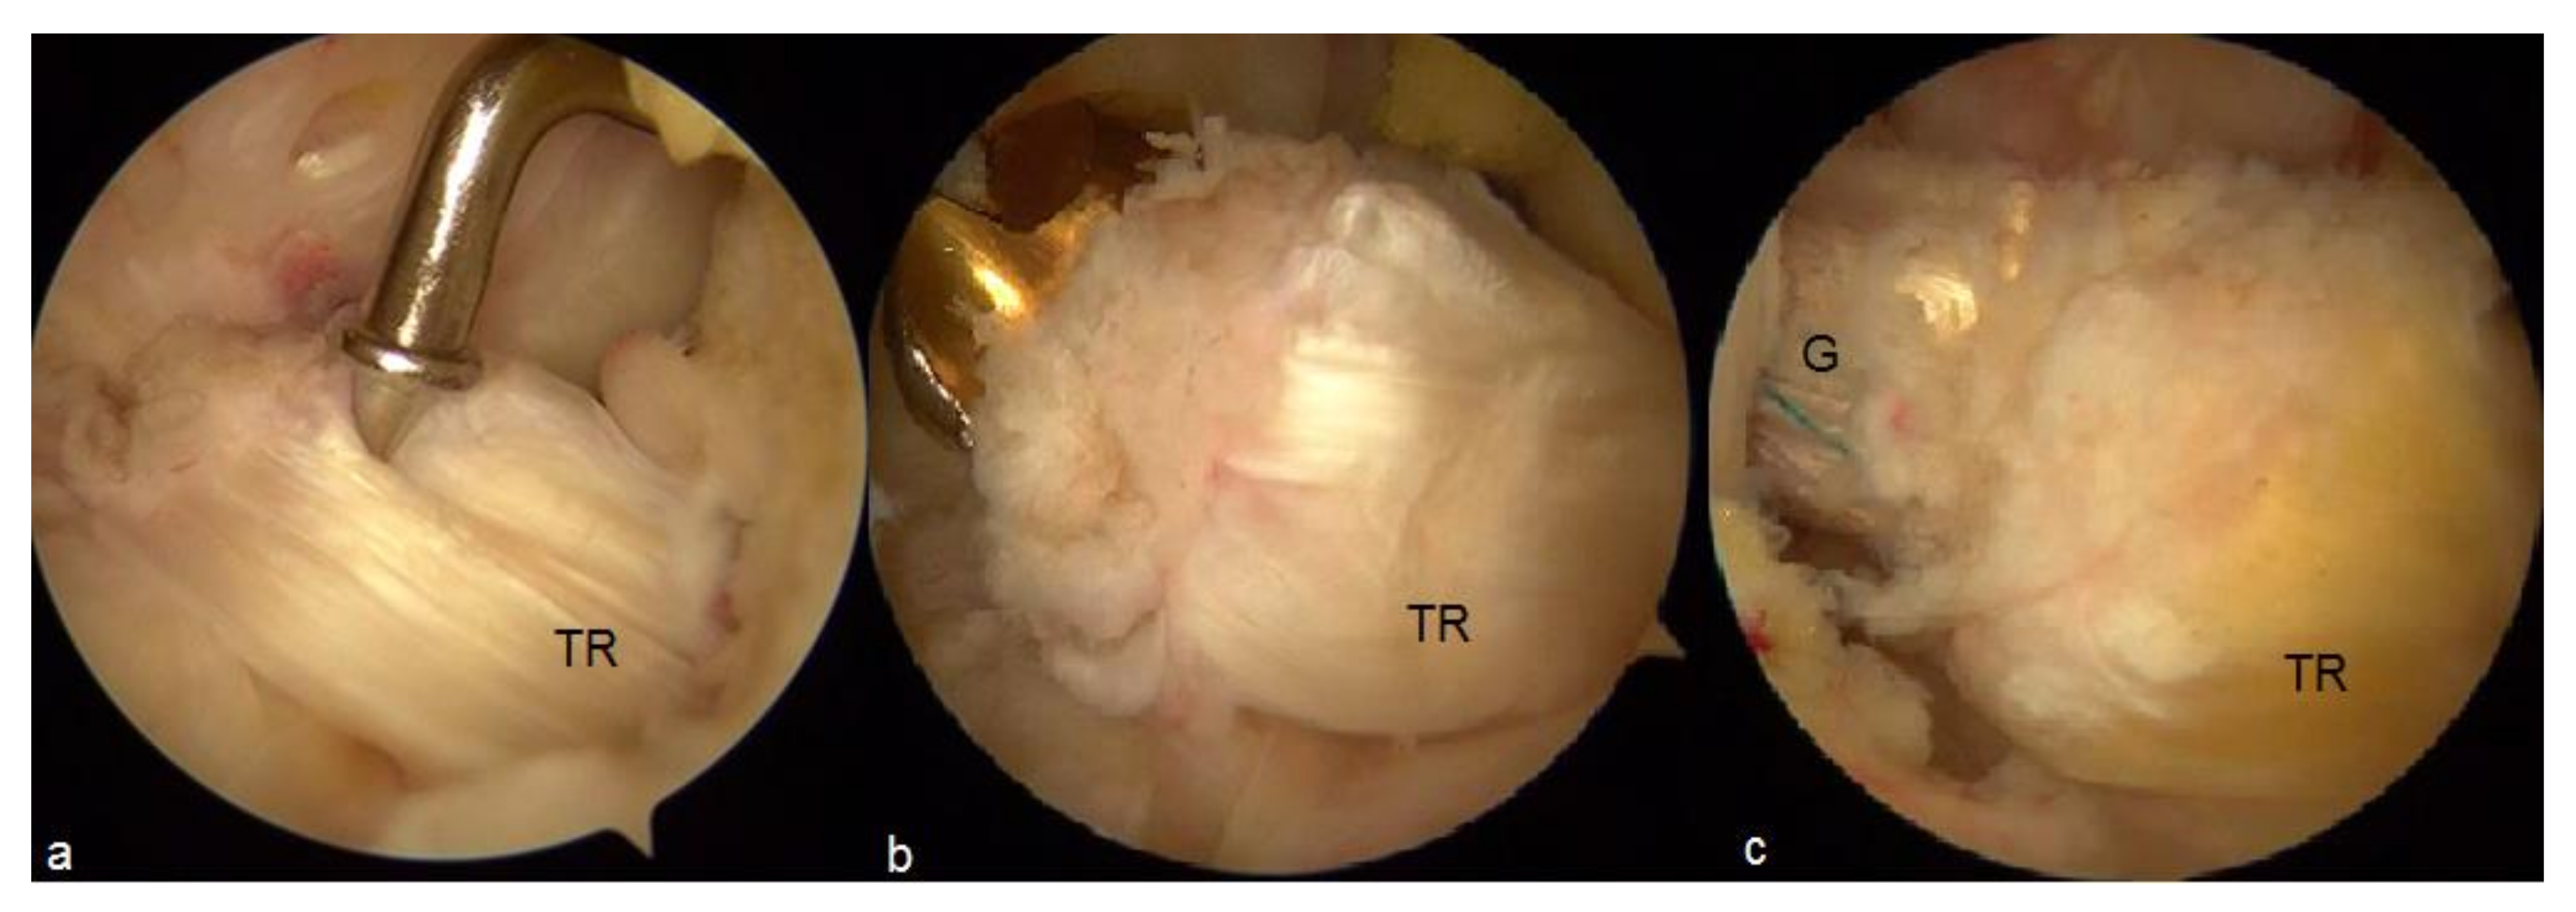

- Malinowski, K.; Ebisz, M.; Góralczyk, A.; Laprade, R.F.; Hermanowicz, K. Synovialization and Revascularization Enhancement in Repaired and Reconstructed ACL: PCL Fat Pad Transfer Technique. Arthrosc. Tech. 2020, 9, e1559–e1563. [Google Scholar] [CrossRef] [PubMed]